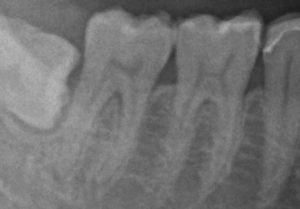

レントゲンを撮ってみるとたしかに虫歯はなさそうです。

ただ親知らず(一番左の横になっている歯)が潜っているので親知らずの周りが腫れたのかな?と疑いお話をさらに聞いてみました、すると